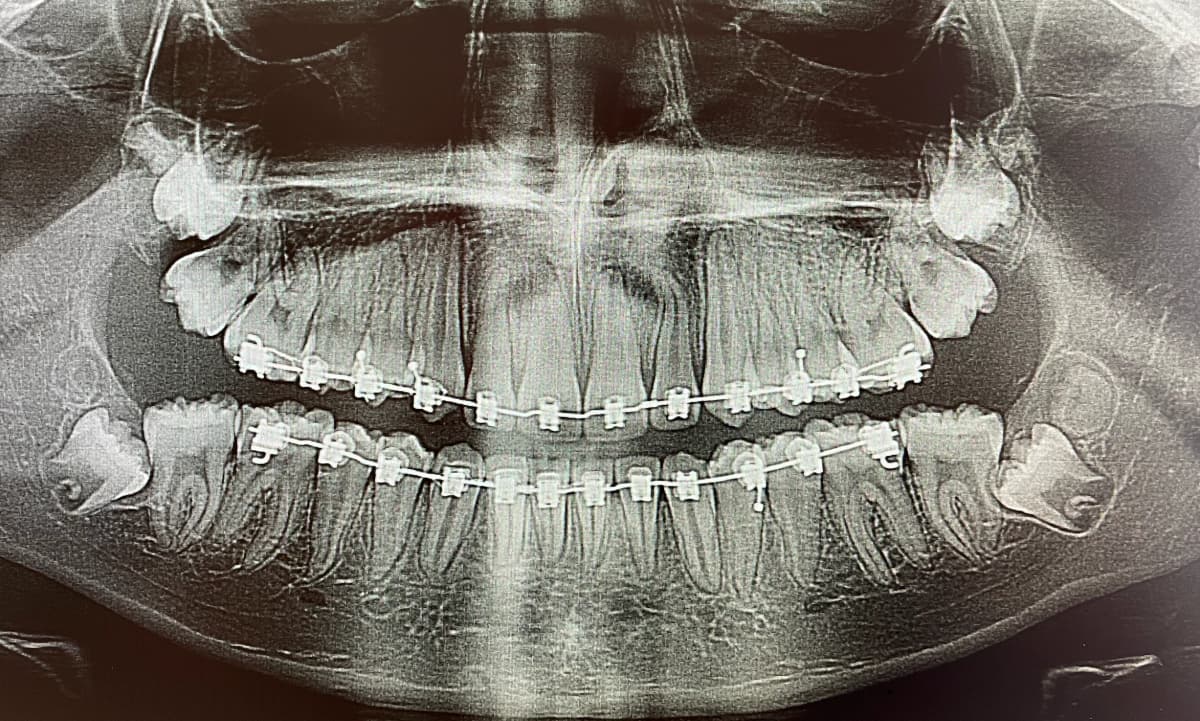

The extraction of wisdom teeth, also known as third molars, is a common dental procedure performed to remove teeth that cannot grow properly or cause dental problems. They are typically four in number and usually appear in the mouth between the ages of 15 and 25. They can fully erupt, be partially erupted, or be impacted. They typically do not have enough space in the mouth, so they are often misaligned and exert pressure on adjacent teeth, potentially causing damage. Extraction of wisdom teeth is often recommended when the teeth are impacted (trapped in the gum or bone) or causing problems such as pain, infection, tooth decay, shifting of other teeth, or the development of cysts. It is advisable to have them extracted at a young age, typically at the end of adolescence or early adulthood. Indeed, the risks increase with age, and recovery is easier at a younger age.